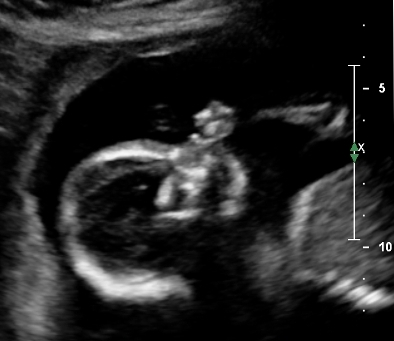

But in the meantime, here’s Louisette sucking her thumb:

I wish she was already here. She’ll be even cuter in colour, 3D, and surround sound.